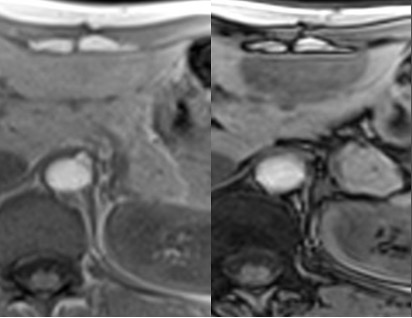

ASCESSO

Raccolta saccata di materiale purulento con distruzione del parenchima epatico e dello stroma.

L’eziologia può essere: biliare (ascendente o colecisti), ematogena portale, ematogena arteriosa, traumatica.

Caratteristiche TC

L’ascesso presenta due segni caratteristici

- Cluster sign: distribuzione segmentaria a grappolo

- Target sign: aspetto trilaminato con ipodensità centrale (necrosi), rim iperdenso (reazione flogistica di parete), vallo esterno ipodenso (edema perilesionale)

Aspetto RM

- Alterazione focale disomogeamente ipointensa in T1, iperintensa in T2, con sfumato alone periferico dato dall’edema perilesionale, caratterizzata da enhancement periferico e ipointensità in fase epatospecifica.

- DWI/ADC: restrizione centrale – componente corpuscolata.